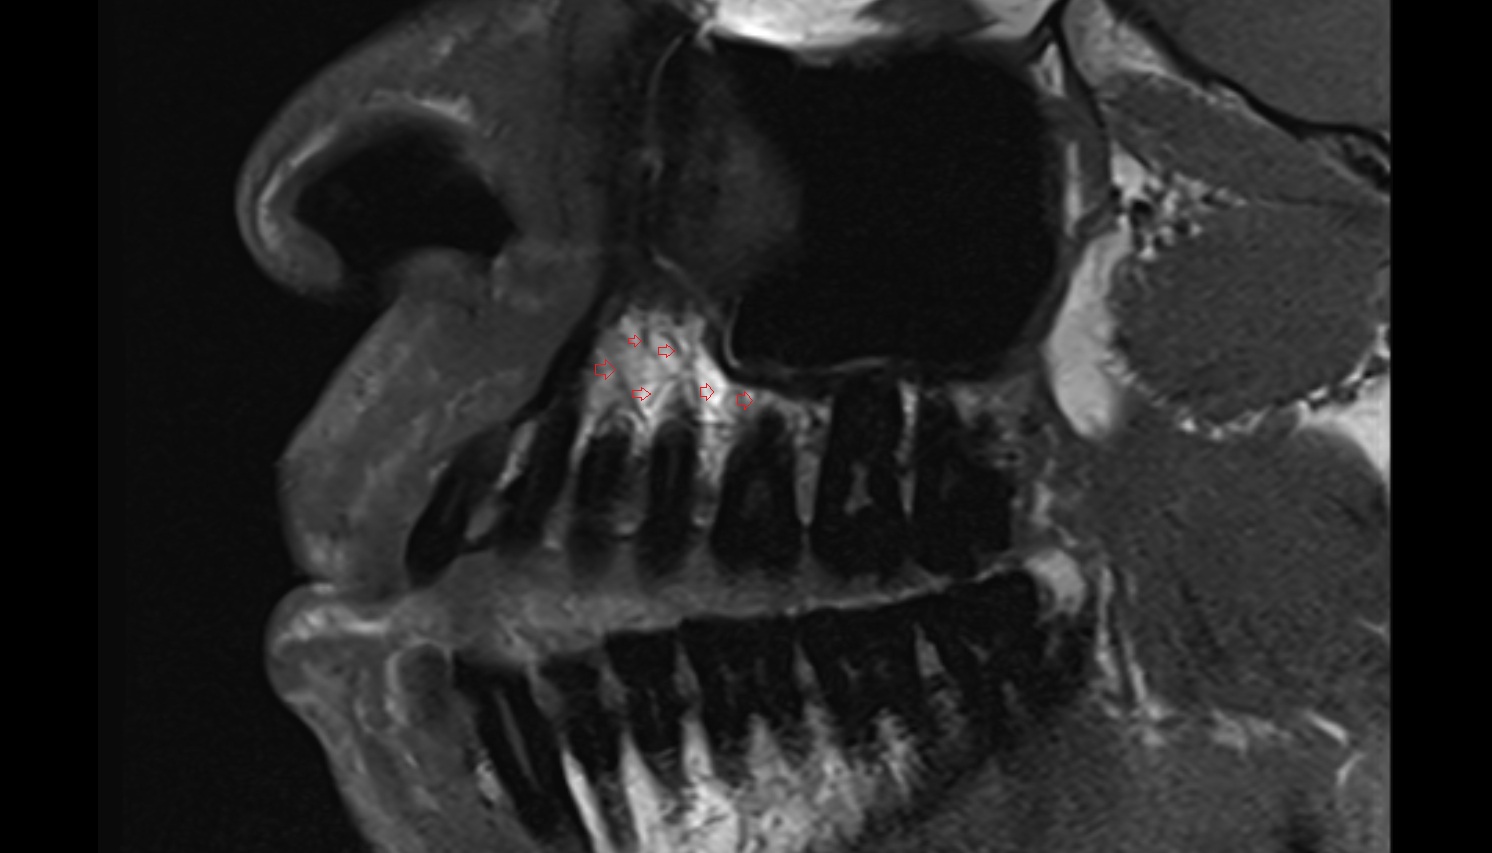

- Temporomandibular joint

- Articular disc of temporomandibular joint

- Articular eminence

- Mandibular condyle

- Mandibular fossa

- Superior head of lateral pterygoid muscle

- Inferior head of lateral pterygoid muscle